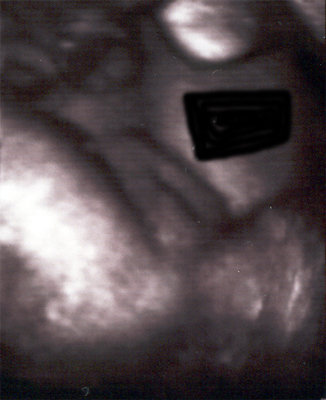

وألحين صور 3D ثلاثية الابعاد

أولا : البنت الاسبوع ال35